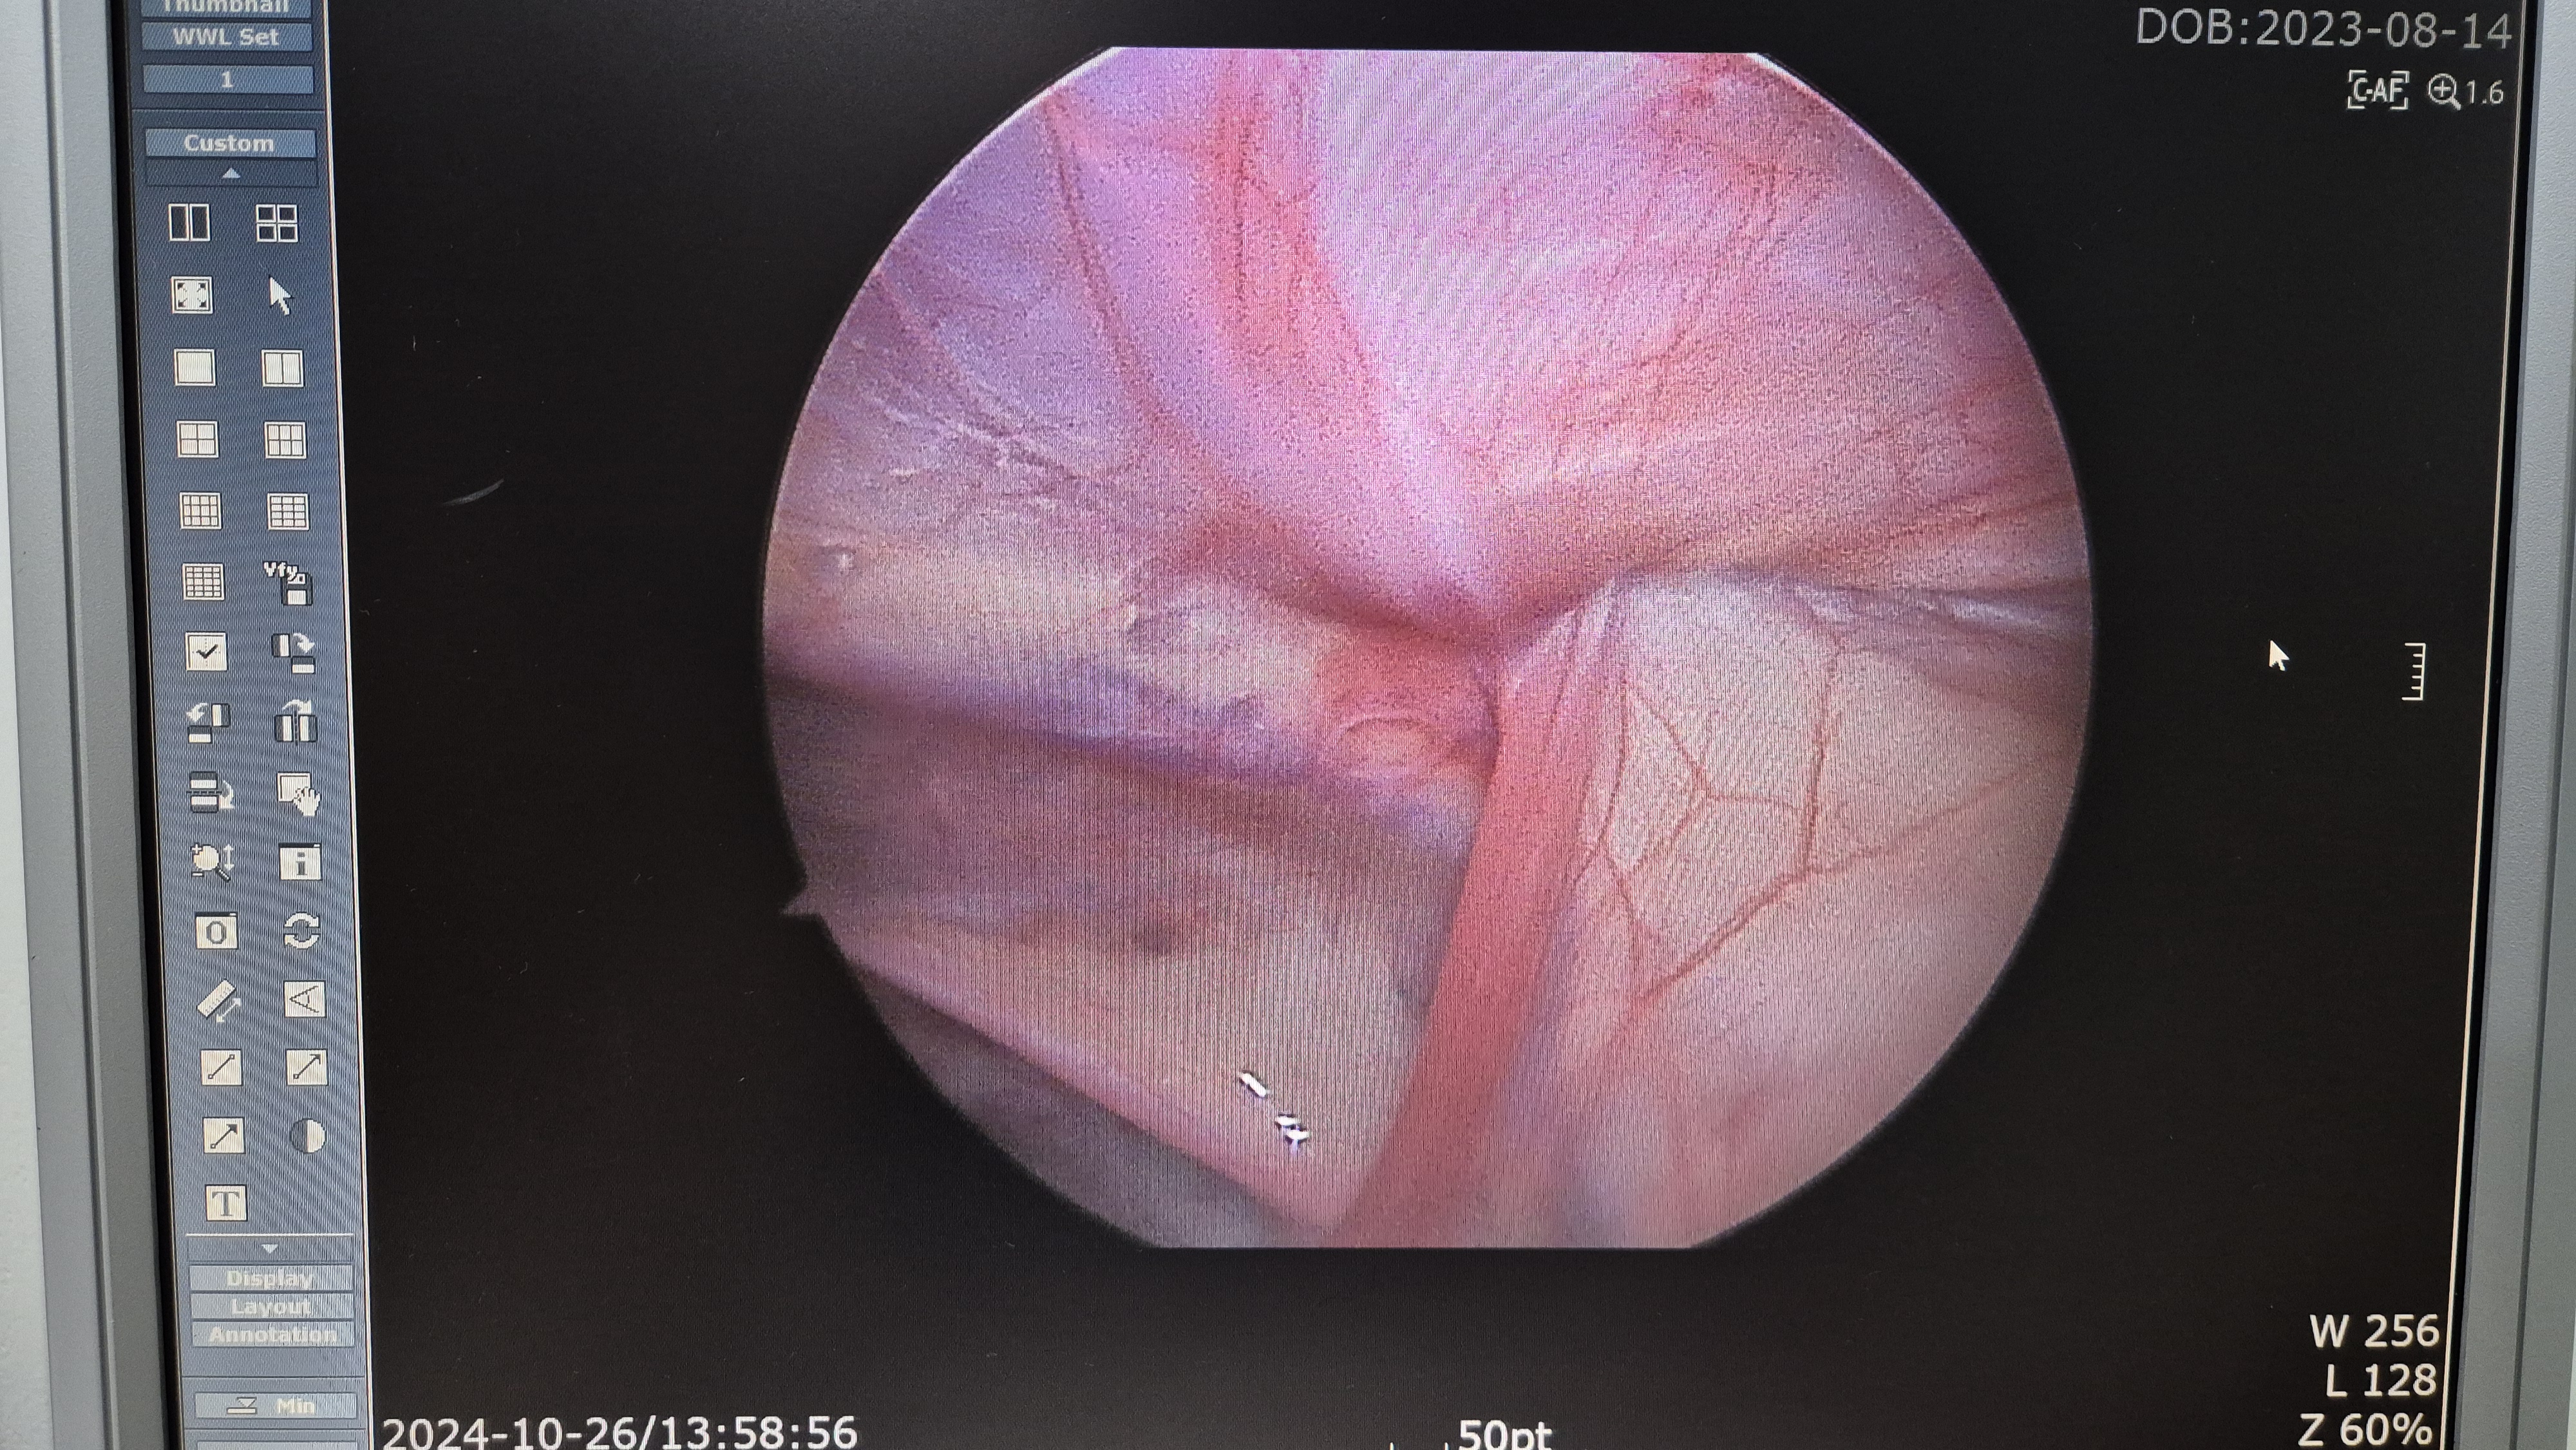

술전 초음파에는 좌측 서혜부 탈장만 확인되었는데 우측에도 탈장 소견이 있습니다.

좌측 서혜부 탈장.